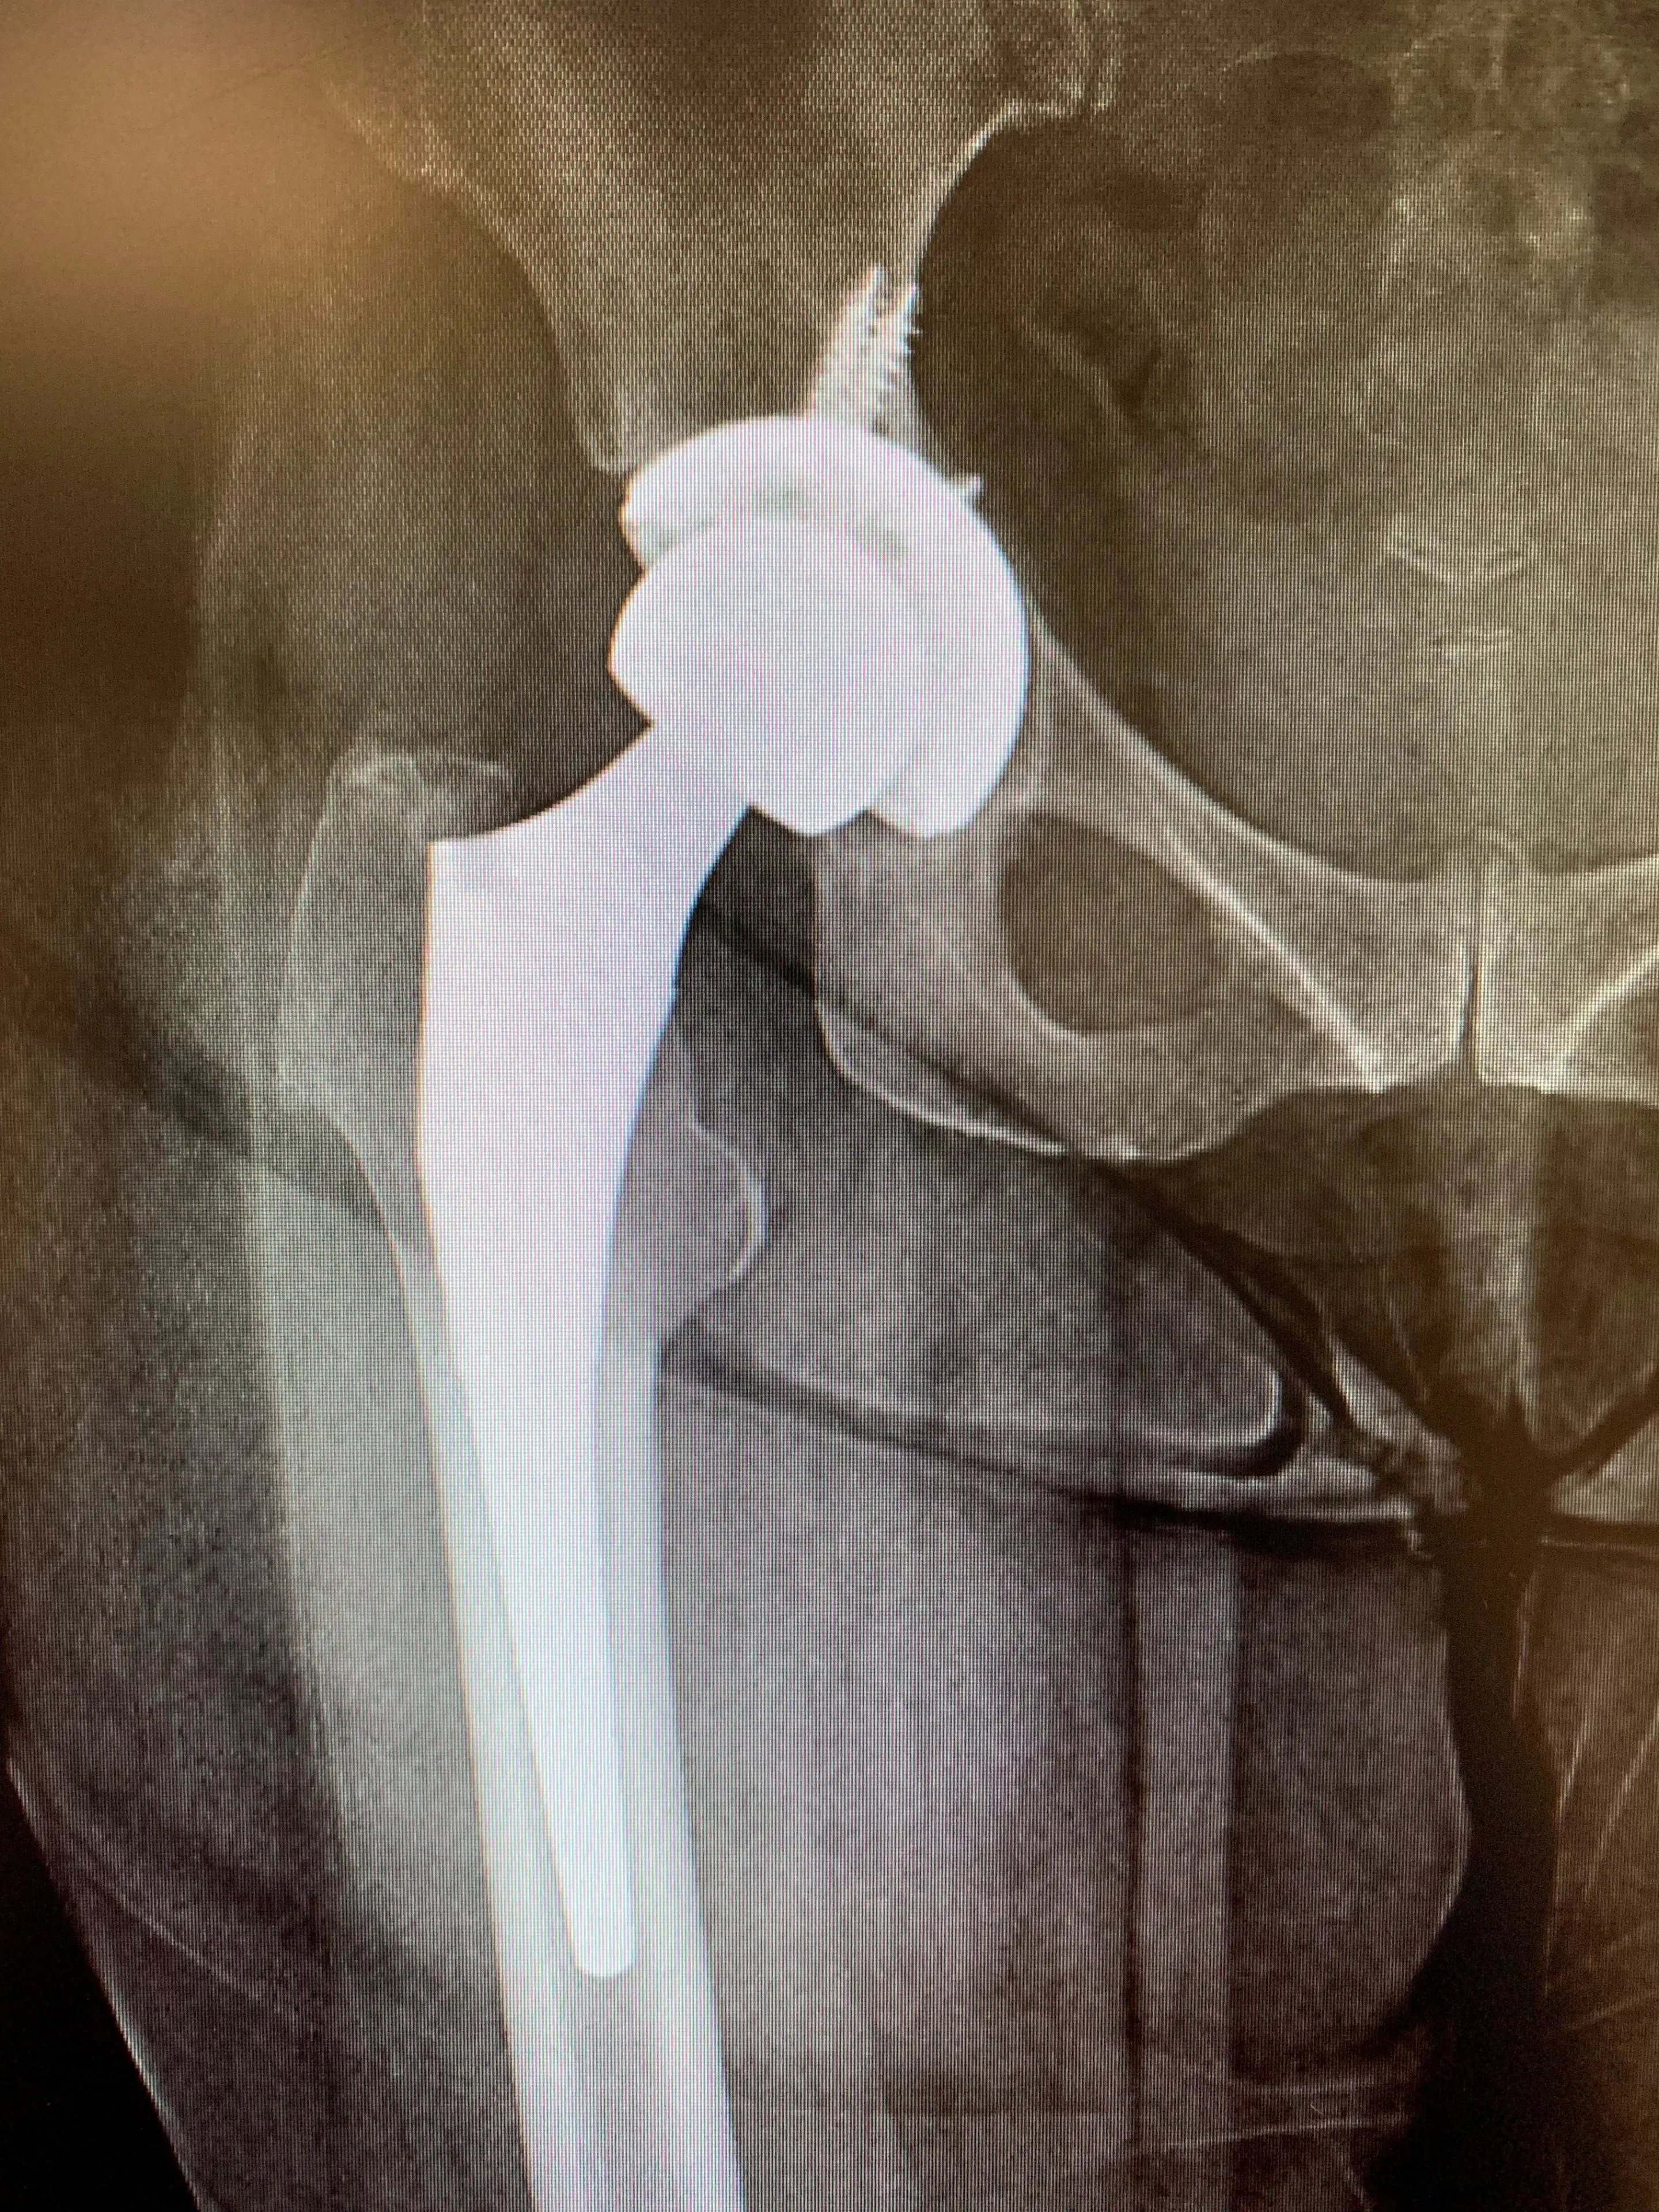

She presented to our clinic with new X-rays that demonstrated asymmetric polyethylene wear in her acetabular component liner. Acquisition of the details of her implants revealed that she did receive an older-generation polyethylene liner, which is known to exhibit signs of wear towards the end of its lifespan.

More detailed examination of her radiographs revealed signs of bone loss around the acetabulum, likely as a result of an inflammatory response generated by polyethylene particles generated from the wear phenomenon. Her femoral component appeared intact with no major issues.

We counselled Mrs. IS that she would require revision surgery of her acetabular component due to her polyethylene wear, and that we would need to revise her entire acetabular component as the type of liner she had implanted is no longer made, but also due to the possibility of loosening of her acetabular component as a result of the bone loss from the polyethylene wear.

She accepted and consented, and we planned for her to receive surgery as soon as possible. We performed a posterior approach – the approach used for her first hip replacement and exposed her artificial hip fully. We dislocated it and used special instruments to first remove her acetabular liner, and then her acetabular component. We observed minimal bone loss, and so placed a slightly larger revision acetabular component in its place, ensuring stability and leg length were both restored.